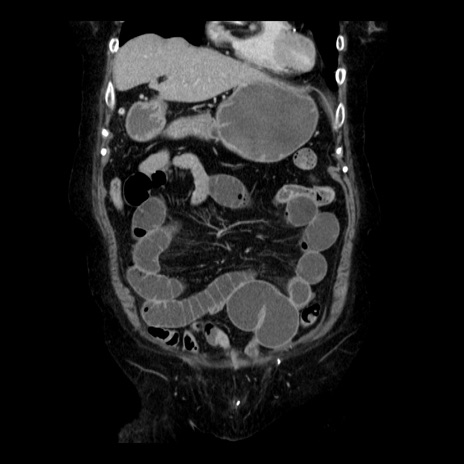

症例14(冠状断像)

【症例】 90歳代女性

【主訴】 腹痛・嘔吐

【現病歴】今朝から左側腹部痛を認めた。 経過観察していたが、嘔吐を認めたため来院。

【既往歴】 子宮癌術後

【身体所見】 意識清明、BP 127/54mmHg、P 98bpm Sp02 95%(RA)、BT 35.8°C、腹部平坦・軟腸ぜん動音聴取良好、右下腹部圧痛(+) 反跳痛なし

【データ】WBC 9800、CRP 0.46